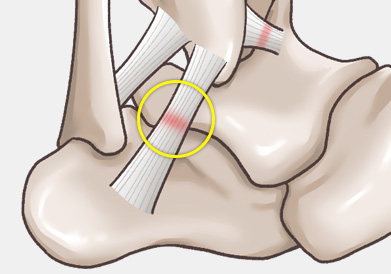

발목 인대는 발목 관절의 안정성을 유지하고, 발의 과도한 움직임을

제한하여 발목 관절을 보호하는 역할을 합니다.

발목 인대 파열은 발목 관절을 지지하는 인대가 외부 충격이나 과도한 움직임으로 인해 늘어나거나 찢어지는 손상을 말합니다.

주로 다음 그림처럼 내반(inversion)에 의해 바깥쪽 인대가 파열되는 경우가 흔하며, 그 중에서도 전거비인대 및 종비인대의 손상 여부가 수술을 결정하는 데 가장 중요합니다.